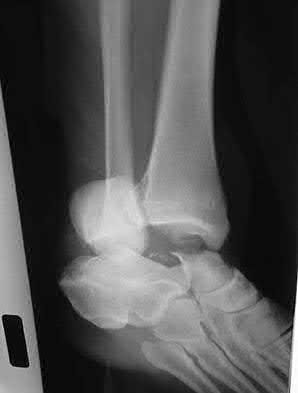

A 34-year-old male sustains the closed injury seen in Figure A as a result of a high-speed motor vehicle collision. What is the most appropriate next step in treatment?

The radiograph shows a comminuted pilon fracture, which is associated with high-energy trauma and significant soft tissue injury. The tested concept here is the importance of avoiding definitive reduction and fixation of this high-energy injury, which has been shown to be associated with an increased risk of wound complications and deep infections (as compared to staged treatment with usage of a spanning external fixator).

Patterson et al. reviewed 23 consecutive patients with comminuted distal tibia fractures. They showed 0% infections or wound-healing problems in their patient population treated with a two-staged protocol. Their protocol involved fibula fixation with an intramedullary implant and application of a medial external fixator to to regain length and restore anatomic alignment. Reevaluation of the limb occurred ten to fourteen days later for definitive fixation.

Sirkin et al. retrospectively reviewed 40 closed and 17 open pilon fractures (AO types 43A-C) that were treated with staged surgical management (avg. time from ext. fix. to formal reconstruction was 14 days (range 4 to 31) They reported 17% post-operative wound complication in the closed group and 11% post-operative wound complication in the open group (Gustilo Type I-III). They suggest the technique was successful in both closed and open pilon fractures.